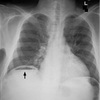

Dx

EPOC